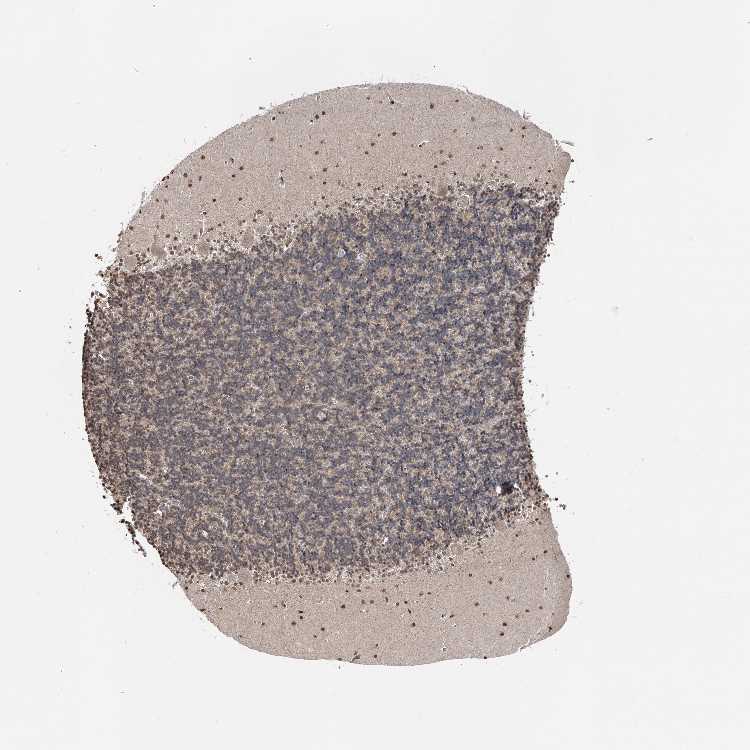

CEREBELLUM - Antibody stainingi

Antibody staining in the annotated cell types in the current human tissue is reported as not detected, low, medium, or high, based on conventional immunohistochemistry profiling in selected tissues. This score is based on the combination of the staining intensity and fraction of stained cells.

Each image is clickable and will lead to virtual microscopy that enables deeper exploration of all samples and also displays staining intensity scores, fraction scores and subcellular localization as well as patient and tissue information for each sample.

Antibody HPA036809Antibody HPA036810

Purkinje cells HighMedium

Cells in granular layer Not detectedMedium

Cells in molecular layer HighHigh